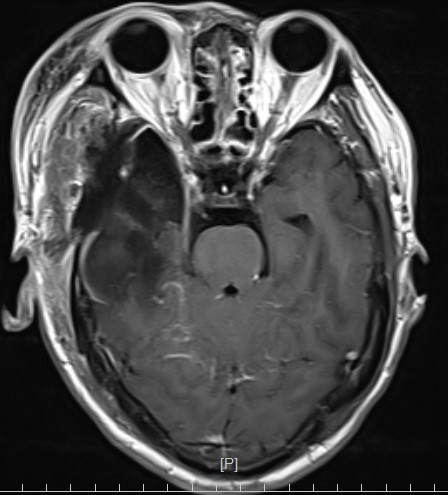

头部MR提示:右颞叶,岛叶及基底节区巨大占位,胶质母细胞瘤可能性大

冠状位